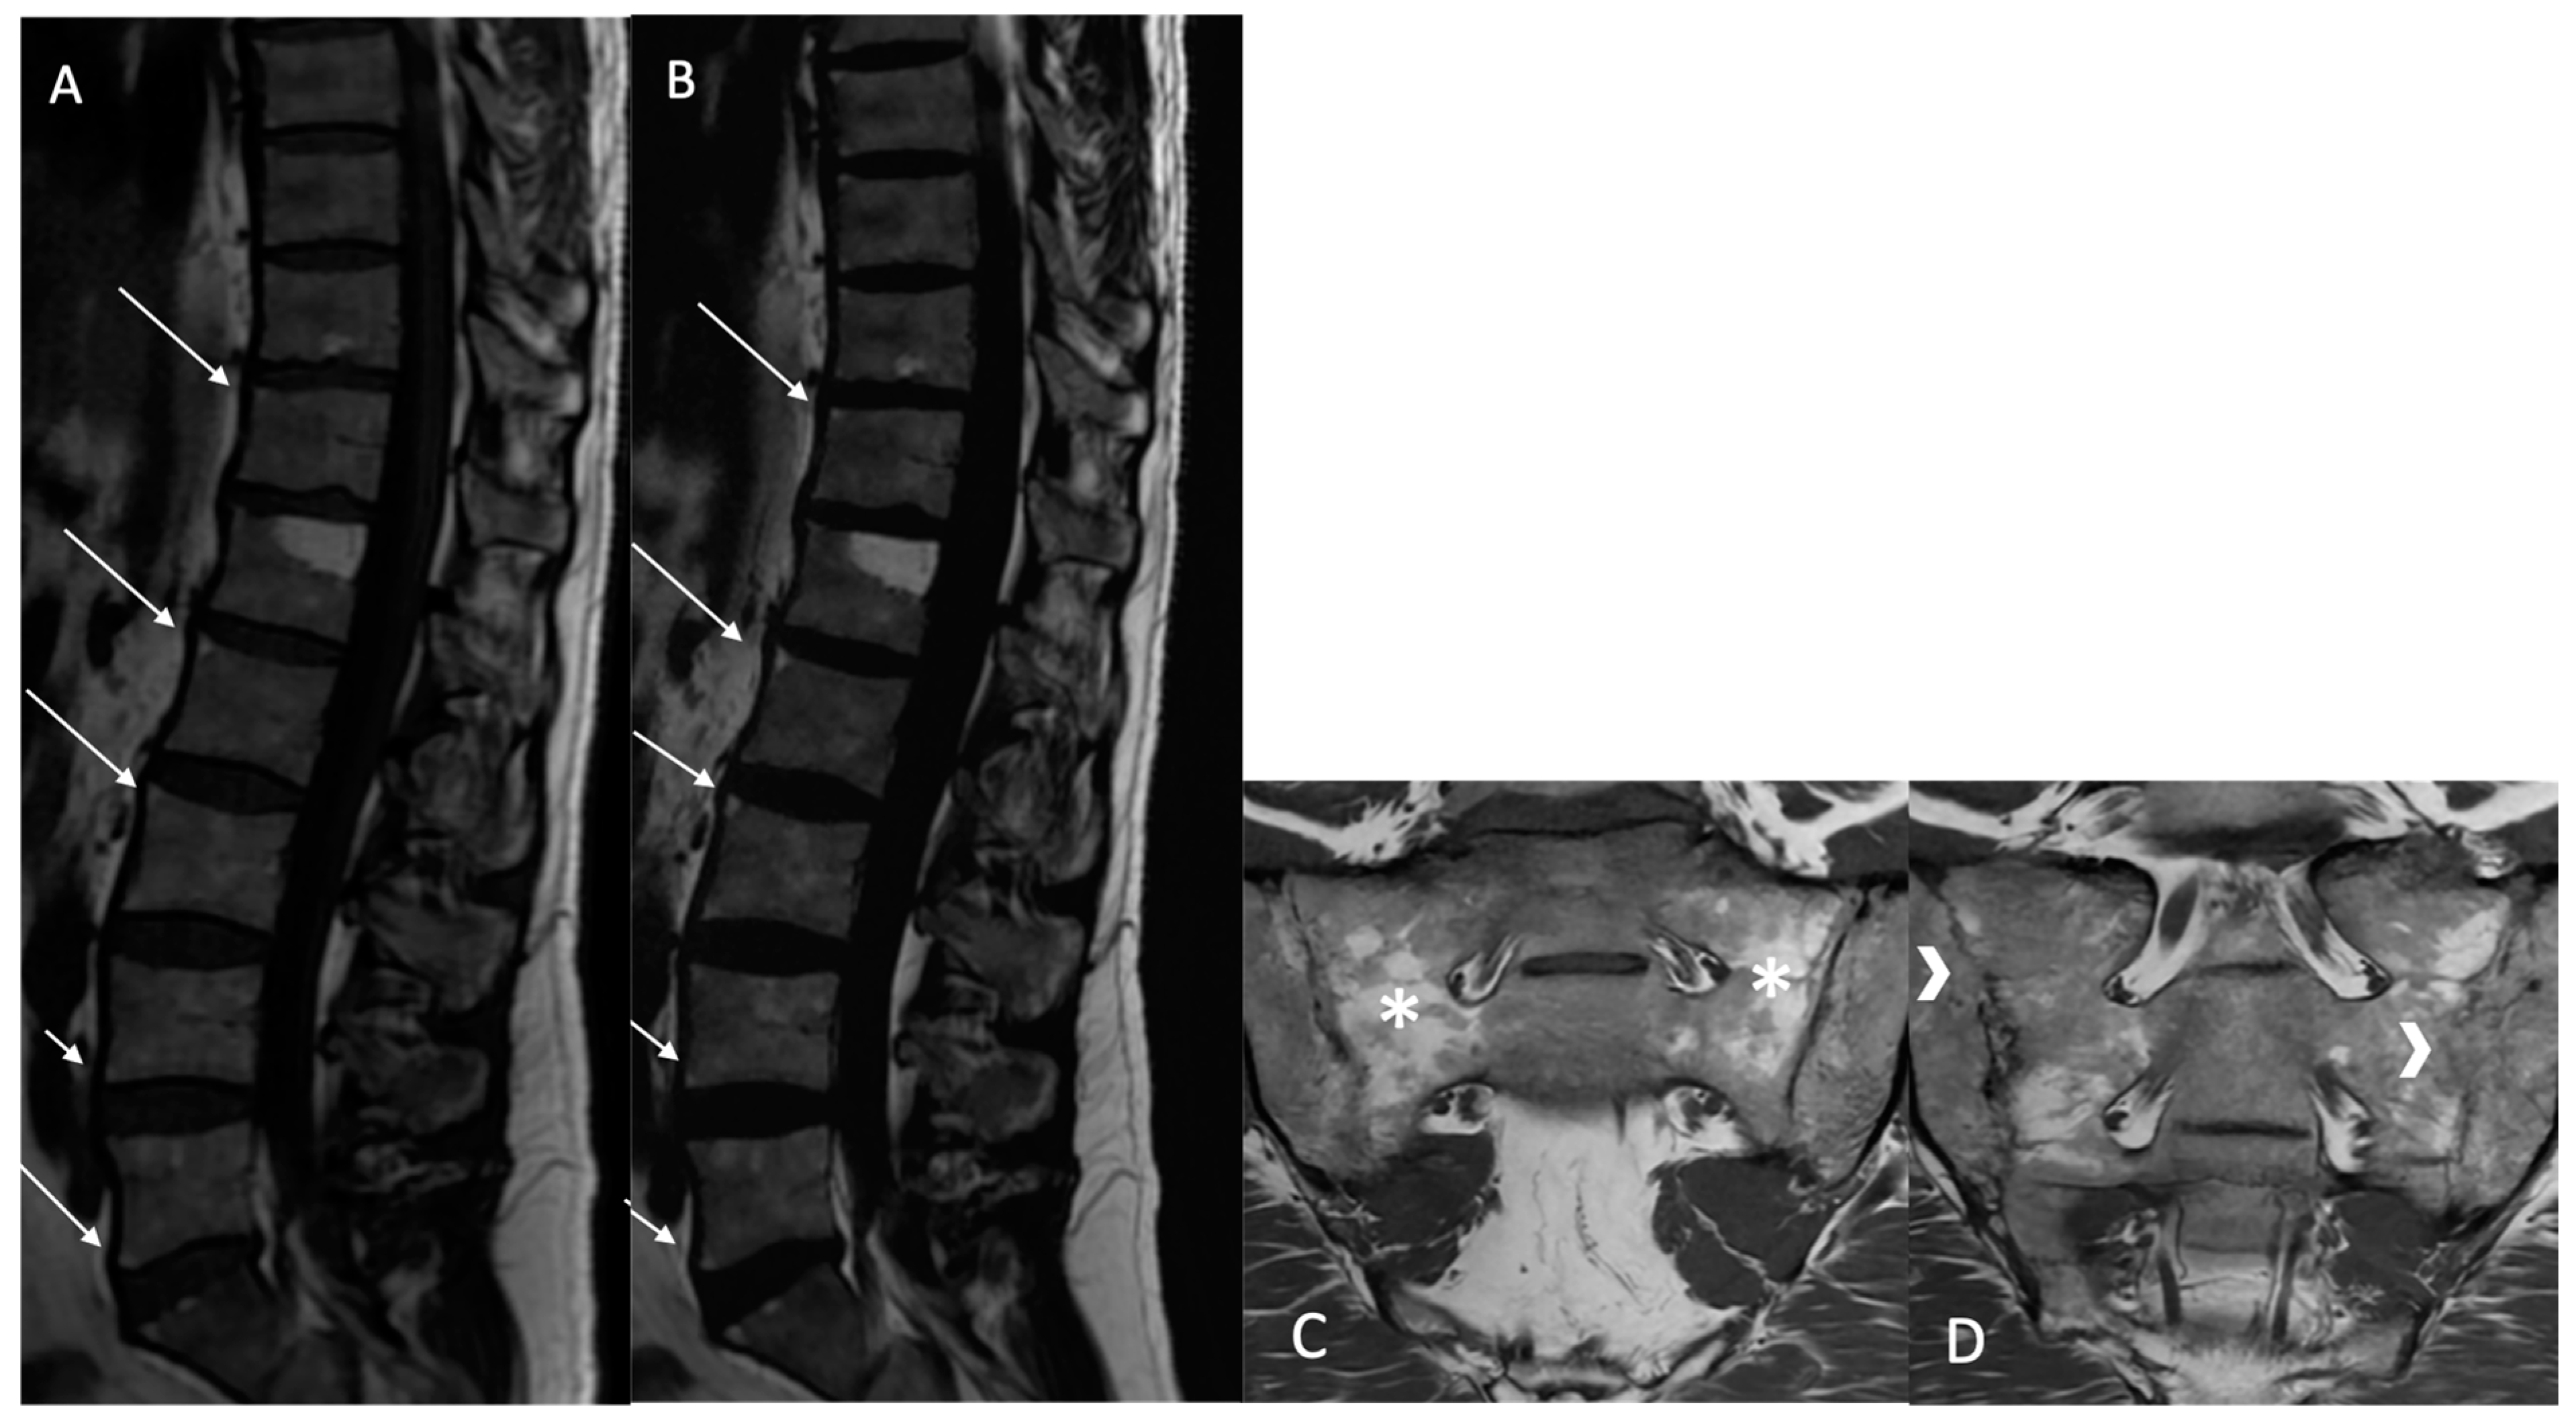

Sclerosis (BMS): Defined as focal, multifocal, or diffuse increased density of the bone matrix, typically showing iso-hypointensity in the skeletal muscle on both sequences (Figure 4).

Figure 4. Multiple fatty lesion (BMF) changes and sclerosis in a 55-year-old patient. A T2 Dixon (water) sequence showing thoracolumbar spondylitis and left sacroiliitis. A T1w sagittal sequence showing BMF localization at the longitudinal ligamentary structure enthesis (arrows). Focal sclerosis is noted at the L3 anterosuperior vertebral corner (circle), and appears as a focal hyposignal (A). A T2w Dixon (fat) image better showing BMF localization (arrows). Erosion areas are surrounded by fatty replacement areas (B). A T2w STIR coronal oblique sequence showing left anterior inflammatory sacroiliitis (arrow) (C).